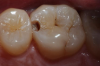

Figure 4 through Figure 11 compare various imaging modalities in three different cases, illustrating the potential of these devices to improve diagnostic capabilities.

Fig 4. Case 1. Bitewing radiograph shows no indication of caries on tooth No. 14.

Figure 4

Fig 5. Case 1. NIR transillumination image of tooth No. 14 shows darkness on the mesial crossing the dentinoenamel junction.

Figure 5

Fig 6. Case 1. Initial opening of tooth reveals caries.

Figure 6